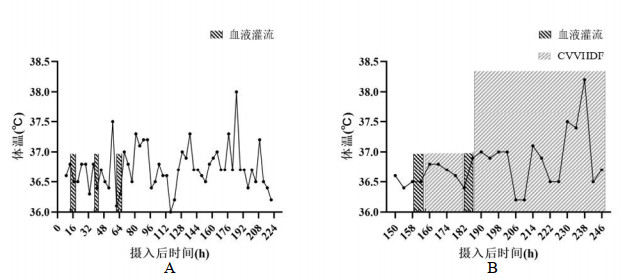

1 资料与方法 1.1 治疗经过病例1是一名70岁男性,因“口服甲维虫螨腈(甲氨基阿维菌素1%,虫螨腈5%)20 mL, 10 h”入院,虫螨腈含量1 g。患者自服杀虫剂5 h后在当地医院予清水500 mL催吐1次。摄入10 h后转至本院,入室查体:T 36.8℃,P 98次/min,R 20次/min,BP 138/83 mmHg,SpO2 97%,心肺腹部均无异常。初步诊断:急性杀虫剂中毒(虫螨腈)。给予乳果糖90 mL、复方聚乙二醇电解质散1 000 mL、20%甘露醇250 mL口服导泻,30%脂肪乳250 mL静脉滴注。摄入毒物后13 h、16 h、38 h、41 h、60 h、63 h共行6次(2次/ d×3 d)血液灌流,动态监测血液中虫螨腈及代谢产物溴代吡咯腈浓度(见图 1A)。摄入毒物后185 h,患者出现一过性体温升高,最高38.0℃(见图 2A),并伴有四肢肌张力增高。第9天患者自动出院,出院后3 d随访无异常,其后失访(通过多种方式未查证到患者死亡信息)。在入室、首次血液灌流1 h、2 h、12 h后,以及灌流3次后、入室第5天、第7天共7个时间点,分别留取EDTA抗凝血2 mL。(住院期间实验室检查见表 1,颅脑影像学检查见图 3A、B)。

| 图 2 入院后病例1(A)和病例2(B)的体温曲线 Fig 2 Temperature curves of case 1 (A) and case 2 (B) after admission |

病例2是一名40岁女性,因“口服虫螨腈虱螨脲(虫螨腈9.5%,虱螨脲2.5%)250 mL 149 h”入院,虫螨腈含量23.75 g。患者自服杀虫剂后家属立即予以催吐1次,摄入毒物后2 h即感全身燥热、多汗。患者拒绝洗胃,当地医院未予特殊治疗。149 h后转至本院,入室查体:T 36.5℃,P 75次/min,R 18次/min,BP 99/67 mmHg,SpO2 98%,神志清楚,心肺腹部均无异常。初步诊断:急性杀虫剂中毒(虫螨腈)。予30%脂肪乳250 mL静脉滴注、血液灌流2次/ d×2 d共4次、持续性血液透析滤过(continuous veno-venous hemodiafiltration, CVVHDF)治疗85 h,动态监测血液中虫螨腈及溴代吡咯腈浓度(见图 1B)。摄入毒物203 h患者出现烦躁、谵妄,230 h转为昏迷状态。237 h患者突发呼吸停止,血压下降至54/36 mmHg,双瞳直径散大至3.5 mm,立即予经口气管插管、机械通气,同时积极抗休克治疗,血压难以维持,患者于摄入247 h后死亡。在入室、首次血液灌流后、第二次灌流后,发病第7、8、9天的6:00和18:00共9个时间点,分别留取EDTA抗凝血2 mL。(住院期间实验室检查见表 1,颅脑影像学检查见图 3C)。

病例1体温间断出现低热,在摄入第8天,出现最高体温为38.3℃。病例2摄入早期即出现自感体热,但无具体的体温数值,入院后给予持续性血液净化治疗,前期体温可控制在37.0℃,后期体温升高37.5~38.3℃。

以上两个病例在疾病不同时期接受不同的血液净化方案,病例1在中毒早期给予3 d共6次血液灌流,其血毒物浓度在最初72 h内没有明显的下降,结合其现有的理化特性推测,首先虫螨腈和溴代吡咯腈的Vd可能较大,在其他脏器广泛分布(本课题组已在动物预实验中发现该现象),不断地释放入血。其次胃肠道对于虫螨腈的吸收部位和速度可能具有特殊性,两个因素使得血药浓度长时间处于较高的水平,下降缓慢,代谢产物溴代吡咯腈的浓度下降期出现的更加滞后。对于病例2,在中毒后期(摄入150 h)给予血液灌流4次,基本可去除消化道持续吸收的干扰。每两次血液灌流血溴代吡咯腈浓度下降率为33.67%和32.99%。但后期持续给予CVVHDF,血溴代吡咯腈浓度下降不明显,甚至出现反跳。因此推测:持续性血液透析滤过清除溴代吡咯腈的能力差,这与物质脂溶性、Vd特性相关。在患者肾功能正常的情况下,溴代吡咯腈血浓度无明显变化,提示其从肾脏代谢量较少。在病程后期给予CVVHDF可以控制体温、稳定内环境,但对减轻脑水肿、挽救生命并无明显作用。其他血液净化方式如血浆置换,对虫螨腈及溴代吡咯腈的清除效果仍需进一步研究评估。